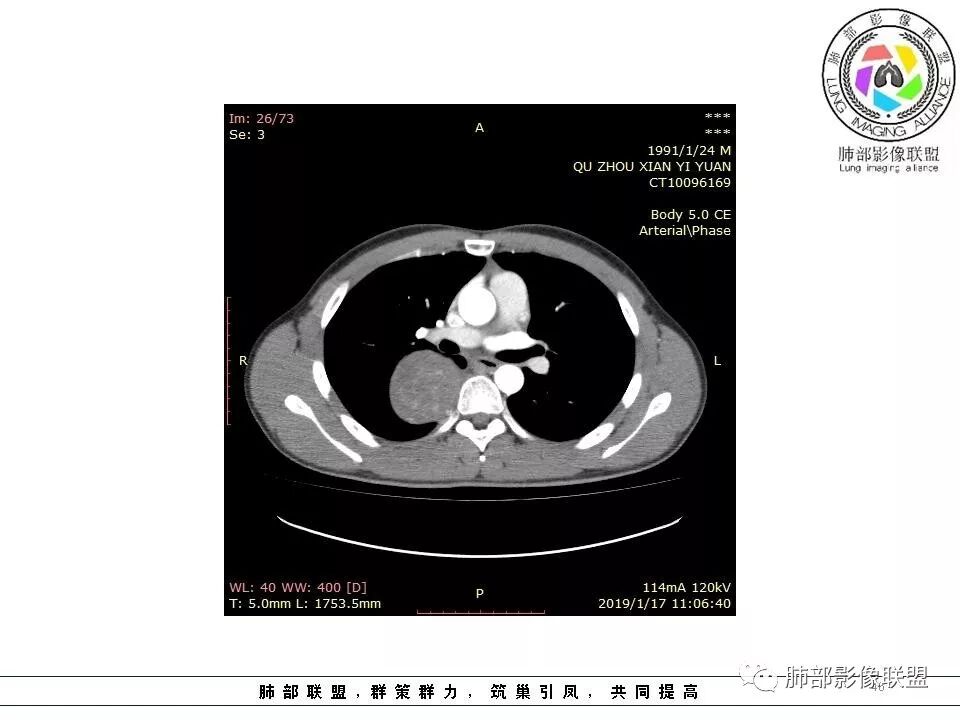

病灶定位脏层胸膜,肺组织受挤压,有胸膜尾征,动脉期可见血管支配,考虑肺动脉供血,静脉期,强化增强明显,符合快进慢出特点,病灶内可见低密度区,考虑胸膜孤立纤维瘤。

青年男性,右侧脊柱旁软组织肿块,边缘膨隆,密度不均,临近肺组织受压、胸膜增厚,增强后动脉期呈不均匀强化,并可见肋间动脉供血,延迟期强化较均匀,定位肺外,首先考虑SFT,神经源性肿瘤待排

右肺占位,跨越上叶后段、下叶背,边缘光滑,瘤肺界面清,见肺压缩缘(线样不张`强化),见胸膜尾征,胸膜下脂肪未见明显增厚,肋骨丶脊柱未见侵袭及受压,渐进性丶地图样强化,冠状位似见体循环供血

右侧后纵膈肿块,有胸膜尾征,周围肺组织及支气管被推压,定位肺外,脏层胸膜来源,血供来自肺动脉或者支气管动脉,增强后持续渐进强化,蛇纹征,考虑SFT,鉴别鞘瘤。

青年男性,胸痛,右上纵膈脊柱旁肿块,形态光整规则,支气管被推移,临近的胸膜明显增厚,有胸膜掀起,增强后密度不均匀,可见蛇形血管征,血供似乎有两根血管供血,考虑SFT

右后纵膈肿块,肺瘤界面清楚,胸膜尾征,邻近肺组织及支气管被推移,部分脂肪间隙存在,定位肺外来源,血供来自肋间动脉,增强后持续渐进强化,蛇纹征,考虑SFT,鞘瘤肿块内血管罕见,不考虑。

右上肺野脊柱旁软组织肿块,边缘光滑整齐,肺组织及气管右肺上叶支气管受压前移,外移,边缘可见胸膜尾征,病灶内密度不均,增强后渐进性持续强化,其内可见明显蛇纹血管征,首先考虑肺外来源,sft.可能性大

青年男性,右侧脊柱旁占位,瘤肺界限清晰,支气管推移,胸膜尾,D字征,胸膜下脂肪影,蛇纹血管,双重供血,延迟强化,定位胸膜,支持sft

青年男性,瘤肺边界锐利,气管向前推移,定位肺外,局部胸膜增厚,后方见少量积液,提示脏层胸膜来源,增强持续渐渐进性强化,内见蛇纹血管,考虑sft

肋间动脉供血,强化尚均匀,逐步强化

供血,体外供血,体循环,要么是壁层胸膜,要么胸膜外的,脏层胸膜应该是对内供血。病变里面的血管,除非是非常粗大迂曲的血管,不然,我不认为是其特点。

脏层胸膜肺内供血,壁层胸膜体外供血

脏层胸膜主要由支气管动脉和肺动脉供血,壁层胸膜主要由支气管动脉,胸廓内动脉、肋间动脉供血

这个病人不是肺动脉与支气管动脉供血,是肋间动脉供血